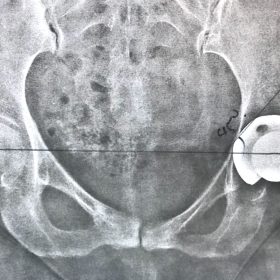

Διάγνωση- Σταδιοποίηση

Διακρίνονται σε 4 στάδια.

Στάδιο Ι. Στένωση του μεσαθριου διαστήματος

Στάδιο ΙΙ. Σκλήρυνση του υποκύμενου χόνδρου

Στάδιο ΙΙΙ. Σκλήρυνση του υπερκείμενου χόνδρου, καταστροφή του υποχόνδρινου οστούν, σχηματισμός οστεόφυτων, οίδημα αρθρώσεως και βραδυνός πόνος

Στάδιο IV. Οστική καθίζηση, καταστροφή μαλακών μορίων μυϊκών ομάδων, υπεξάρθρημα της αρθρώσεως και αλλαγή του μηχανικού άξονα